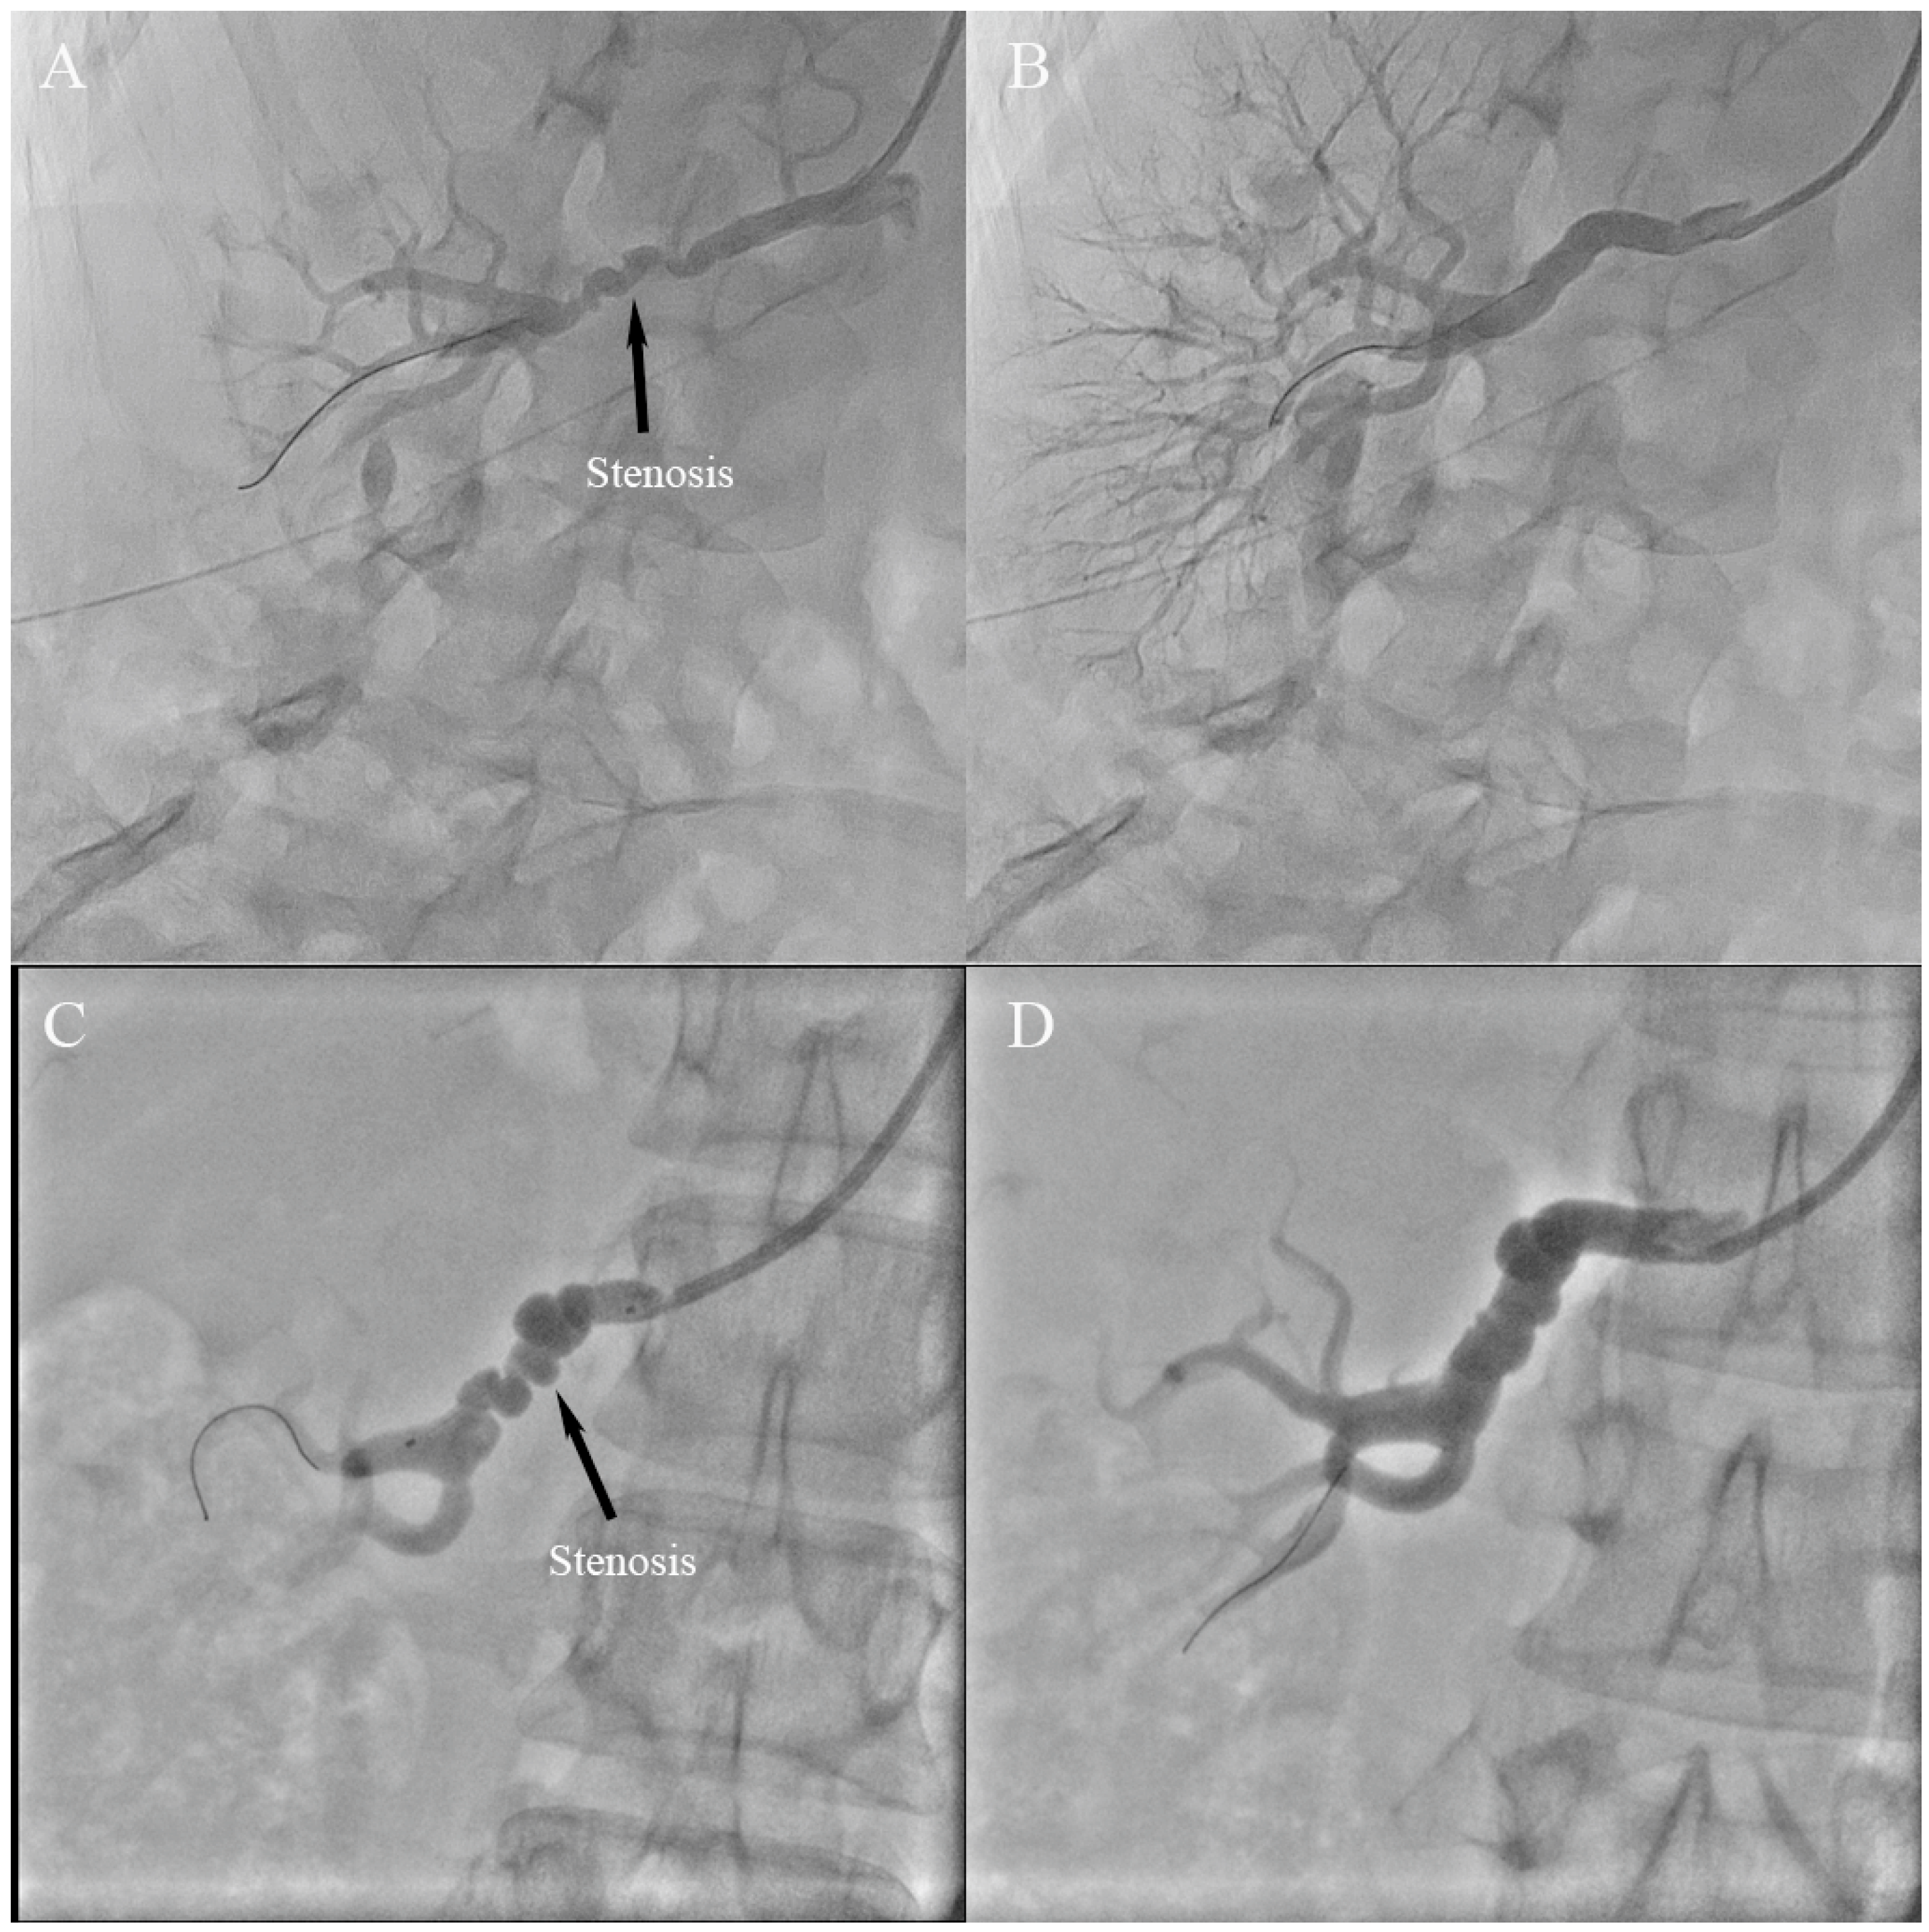

3.2. Angiographic Findings and Treatment